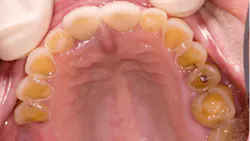

Dental erosion is a chemical process characterized by acid dissolution of dental hard tissue resulting in an irreversible loss of tooth structure. Acid destruction of the dentition occurs with both extrinsic and intrinsic factors. Extrinsic factors are caused by bacteria that produce acidic byproducts in persons that have diets high in sucrose and poor oral hygiene, or diets that are high in acidity. Intrinsic factors such as acid reflux or the purging associated with BN are also causative effects.5 Perimolysis is a specific form of tooth erosion that’s caused from intrinsic factors without bacterial involvement6 (figures 1,2).

Discolored teeth are the result of tooth erosion and loss of enamel, which is whiter in color than dentin, which is more yellow. Once the enamel is gone, a darker colored and weakened tooth remains that is subject to fracture and is more susceptible to tooth decay.

Dental patients with eating disorders may also present as physically healthy and be considered ASA I patients. Therefore, it is prudent for practicing dental hygienists and dentists to be familiar with the oral manifestations of eating disorders so that they can recognize the oral signs of an eating disorder and refer the patient for proper treatment.2,3,5,8 Particularly, identification of the early signs of periomolysis before more enamel is lost as seen in Figures 1, and 2 is considered optimal.